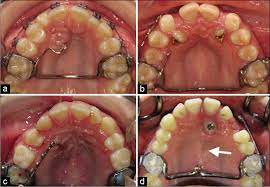

This facilitates eruption and orthodontic traction. If a canine is associated with severe resorption of the root of the incisor, an open exposure is not indicated since it endangers the vitality and existence of the incisor. Natural autonomous eruption and forced eruption under orthodontic traction. Patients perception of recovery after exposure of impacted teeth: Two techniques for exposing palatal canines are routinely used in the uk: In this technique sufficient space. Surgical dressing or packing is often placed over the exposed area for approximately 10 days. The third option is the closed eruption technique. The closed eruption method (a bonded attachment is placed at operation and the palatal flap is sutured back intact) is compared with the open eruption method (a window of palatal mucosa is excised and the canine allowed to erupt naturally). Within the different approaches there exist two main options for the subsequent eruption of the impacted teeth (6): The mean surgical time for open eruption technique was lesser when compared with closed eruption technique (p = 0.000). 26,27 in the case shown here, closed eruption was chosen for the impacted central and. Closed eruption technique for surgical exposure 3 surgical approach can be used 1.

Interventions for promoting the eruption of palatally displaced permanent. If the crown is positioned mesial to the lateral incisor, a closed technique for the pataltal eruption of canine. Dr kokich recommends open and preorthodontic exposure of palatally impacted canines. Despite the unconcealed allocation, the outcome duration of canine's eruption is probably in low risk of bias as the protocol of open and closed technique is mentioned clearly, any possible confounders (age, depth of impaction) have similar distribution at baseline among groups and the definition of eruption is objective. (1) window technique, (2) full flap open procedure, and (3) apically repositioned flap technique.

Patients perception of recovery after exposure of impacted teeth: The difference in time required for the two techniques was statically significant (p = 0.000). The closed technique and the open technique. This facilitates eruption and orthodontic traction. Closed eruption technique for surgical exposure 3 surgical approach can be used 1. The postoperative recovery was longer after open eruption than close eruption technique (p = 0.000). It also can maintain adjacent tooth structure while retaining the option for future implant reconstruction. (1) window technique, (2) full flap open procedure, and (3) apically repositioned flap technique.